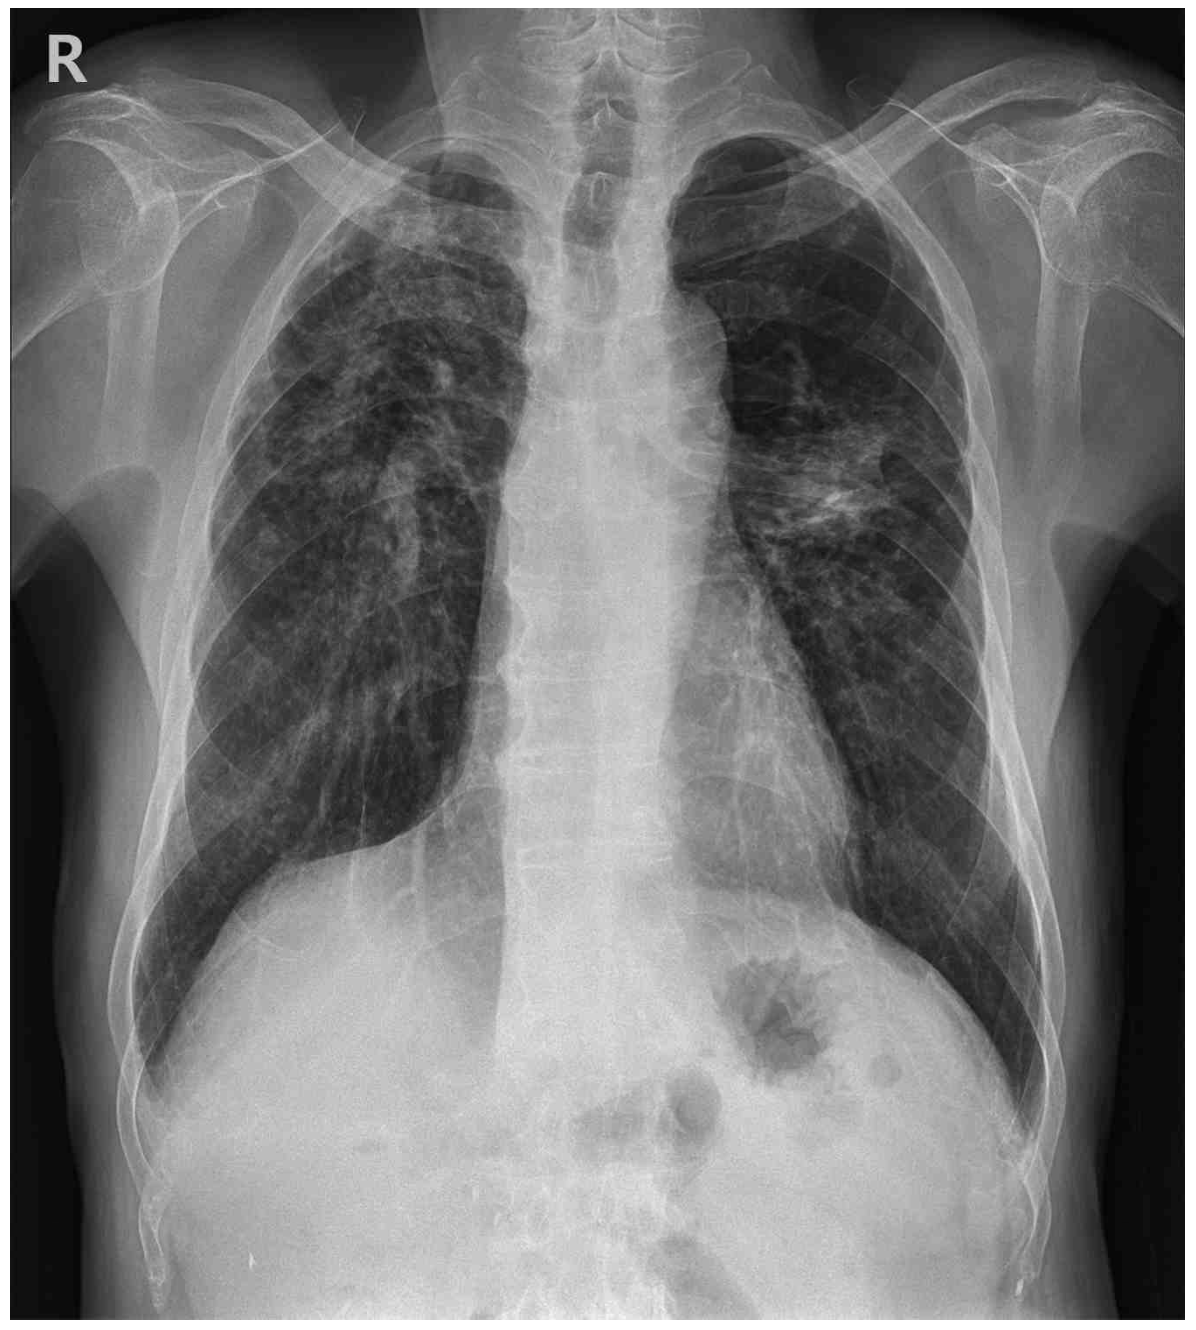

CXR: Bilateral patchy consolidation

• 흉부 X선 검사에서 양측 폐야에 patchy consolidation이 관찰되었으며, 흉부 컴퓨터단층촬영에서 다수의 결절, 종괴 및 간유리 음영이 확인되었다. 특히, 상엽 부위에서 대칭적으로 위치한 종괴가 관찰되는 점을 고려할 때 규폐증으로 인한 진행성 거대 섬유화 가능성이 높다고 판단된다.

• 규폐증을 진단하기 위해서는 silica에 대한 노출력, 특징적인 영상 소견, 그리고 유사한 증상을 유발할 수 있는 다른 폐질환이 배제되어야 한다. 해당 환자의 경우, 22년간의 직업력과 진행성 거대 섬유화를 시사하는 영상 소견이 확인되고 있으며, 타 질환을 의심할만한 소견이 제시되지 않았으므로 만성 규폐증으로 진단할 수 있다.